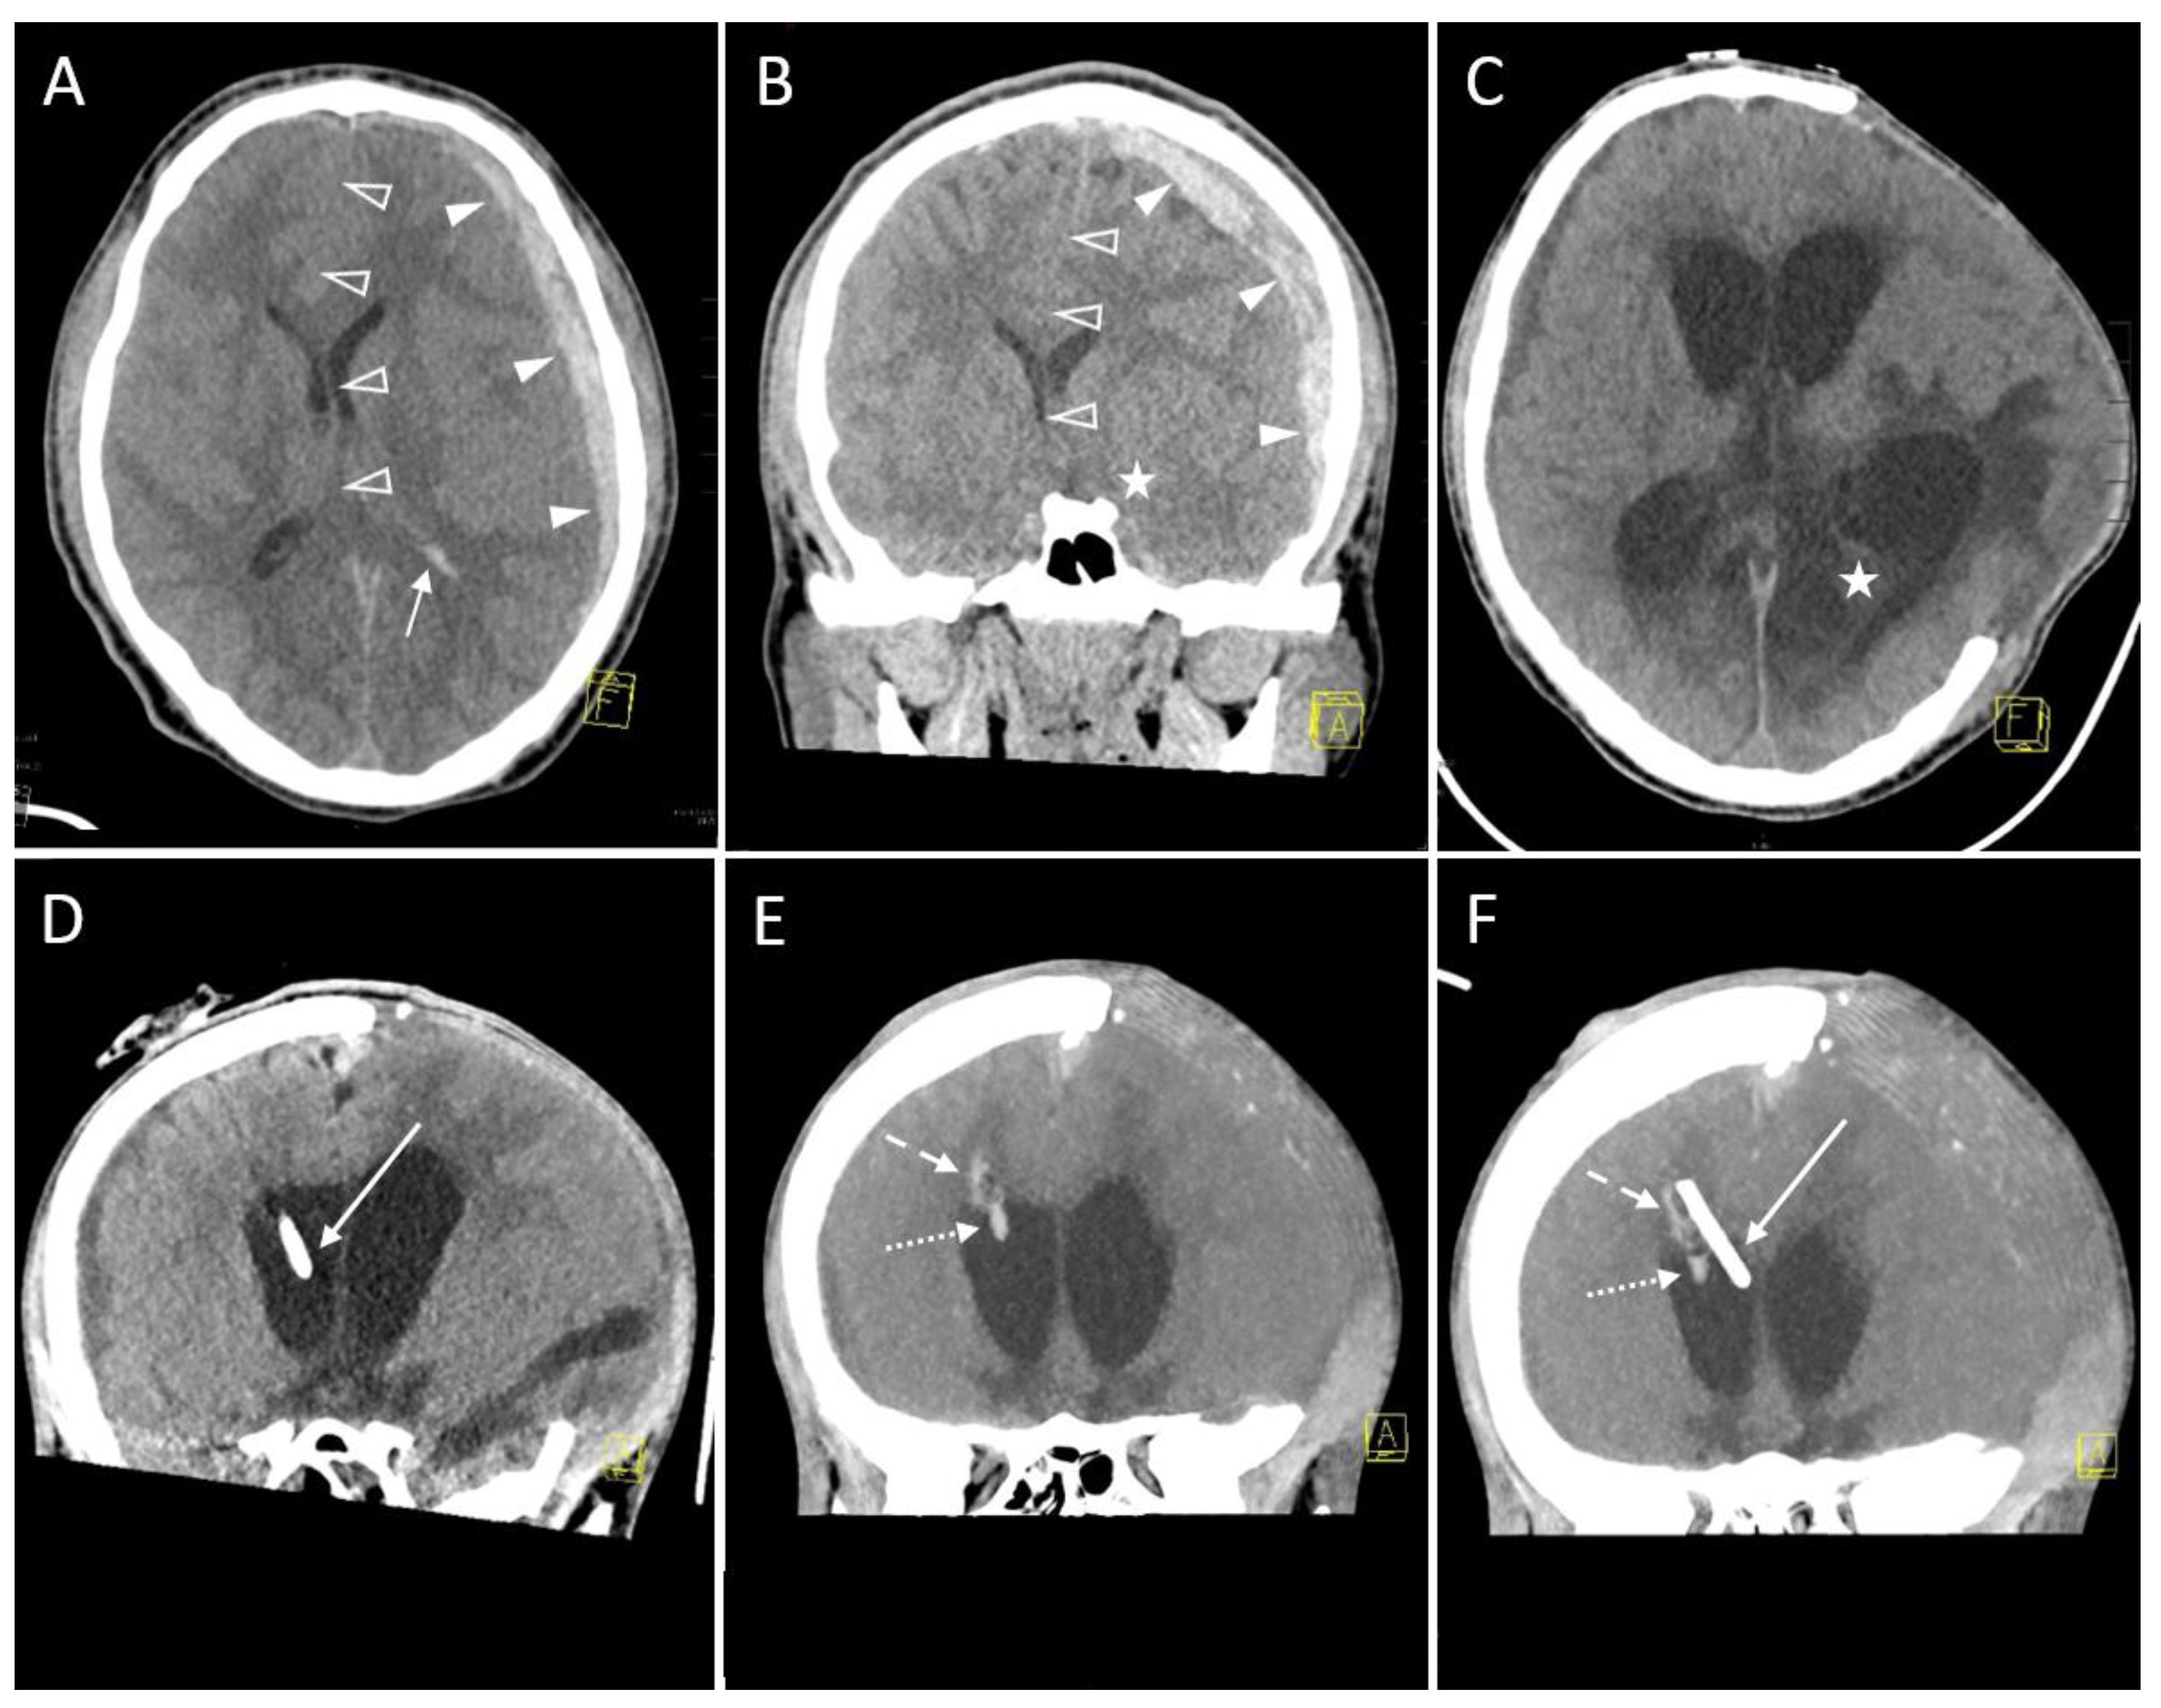

3.2.4. Hemorrhage

| Hemorrhage on follow-up CT | |

| No evidence of hemorrhage | 32 (88.9) * |

| Grade 1 (<1 mL) | 3 (8.3) * |

| Grade 2 (≥1 to 15 mL) | 1 (2.8) * |

| Grade 3 (>15 mL) | 0 (0.0) * |